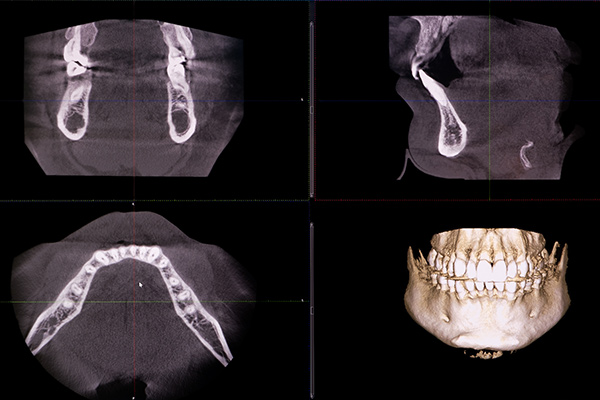

断層写真を画像処理することで、従来のレントゲンではわからない、あごの骨や歯の状態、神経、血管の位置を立体的に観察できる機器です。根管治療やインプラント治療、親知らずの抜歯などにおいて、安全かつ精密に治療計画を立て、施術につなげるために不可欠な設備です。